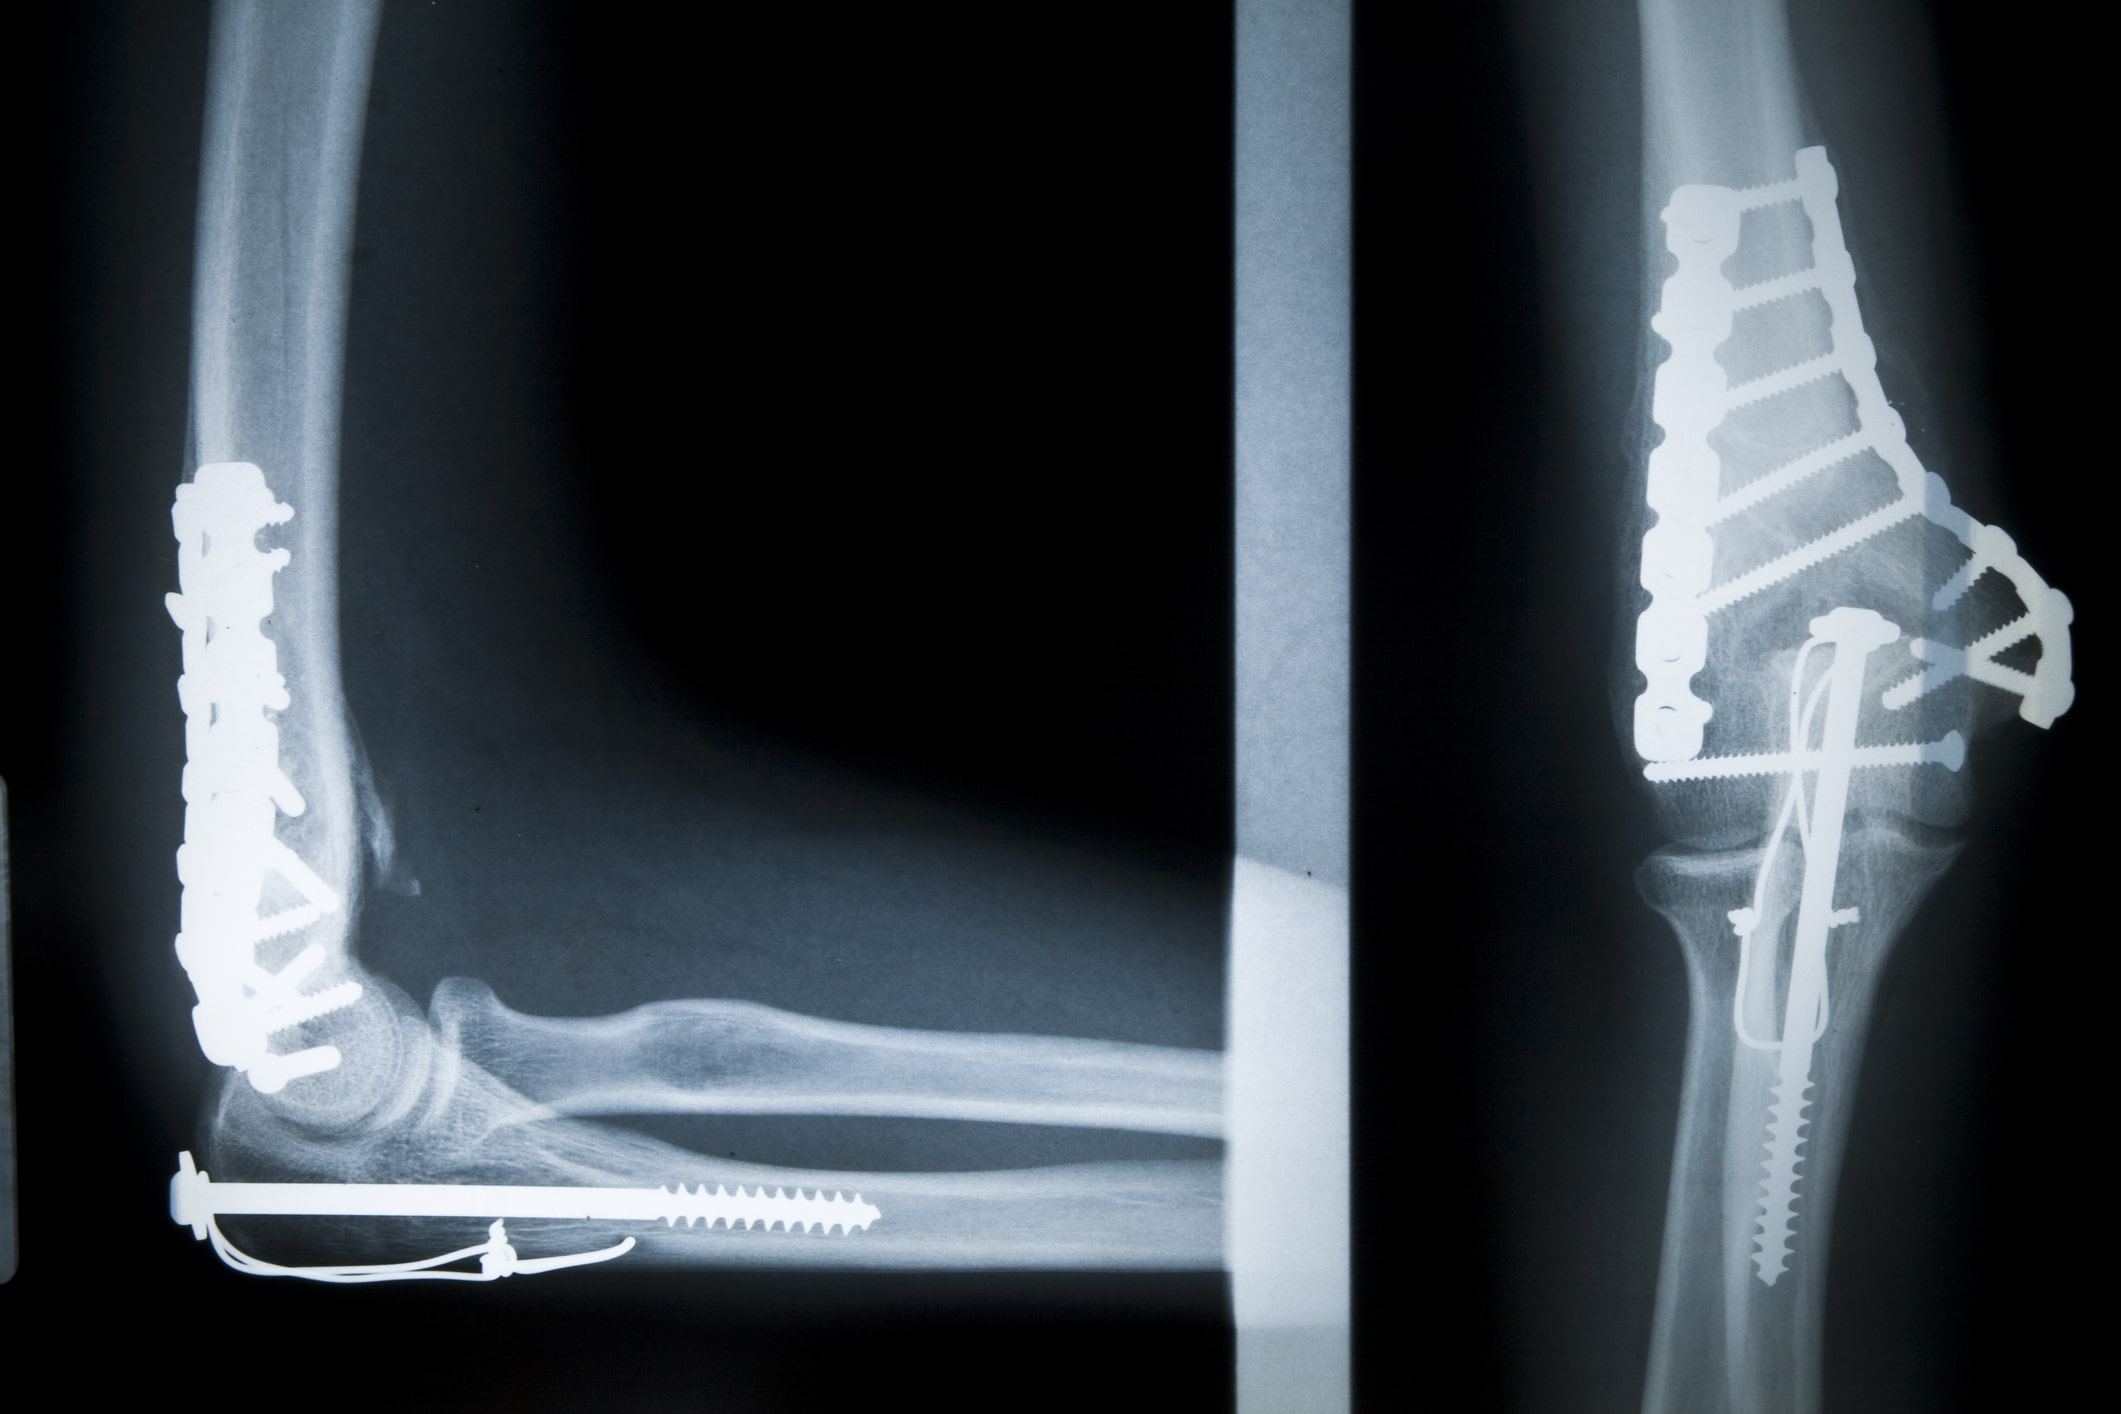

Bei einer Operation zur Behandlung einer distalen Humerusfraktur werden die gebrochenen Anteile wieder an ihre ursprüngliche (anatomische) Stelle gebracht und mittels Metallplatten, Schrauben und Drähten stabilisiert. In Einzelfällen sind noch zusätzlich gewisse Bandnähte oder Ähnliches notwendig.

Der erste Kontrolltermin findet meist ein bis drei Tage nach der Operation statt, um die Wundheilung und den Behandlungsverlauf zu überprüfen. Zudem wird nach der Operation ein Röntgen durchgeführt. Weitere Röntgen sind in der Regel nach 2 Wochen (bei Nahtentfernung), nach 6 Wochen, nach 12 Wochen sowie nach 52 Wochen empfohlen.